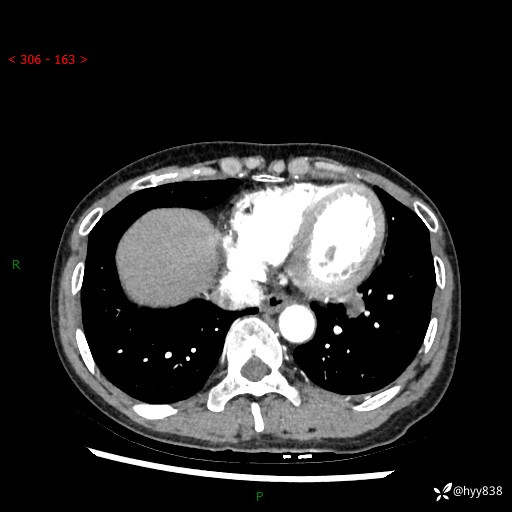

【检查】:胸部CT平扫+增强

各期CT值:40hu 57hu 49hu